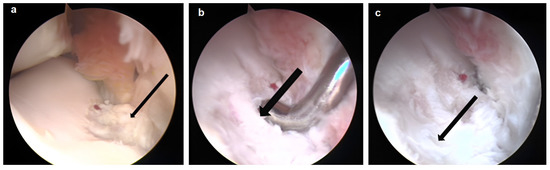

3.2. Arthroscopic Evaluation of the Lesion Site